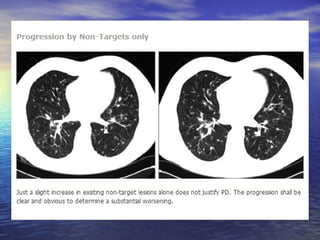

Exemplo de progressão de lesões não alvo

Progressão de doença